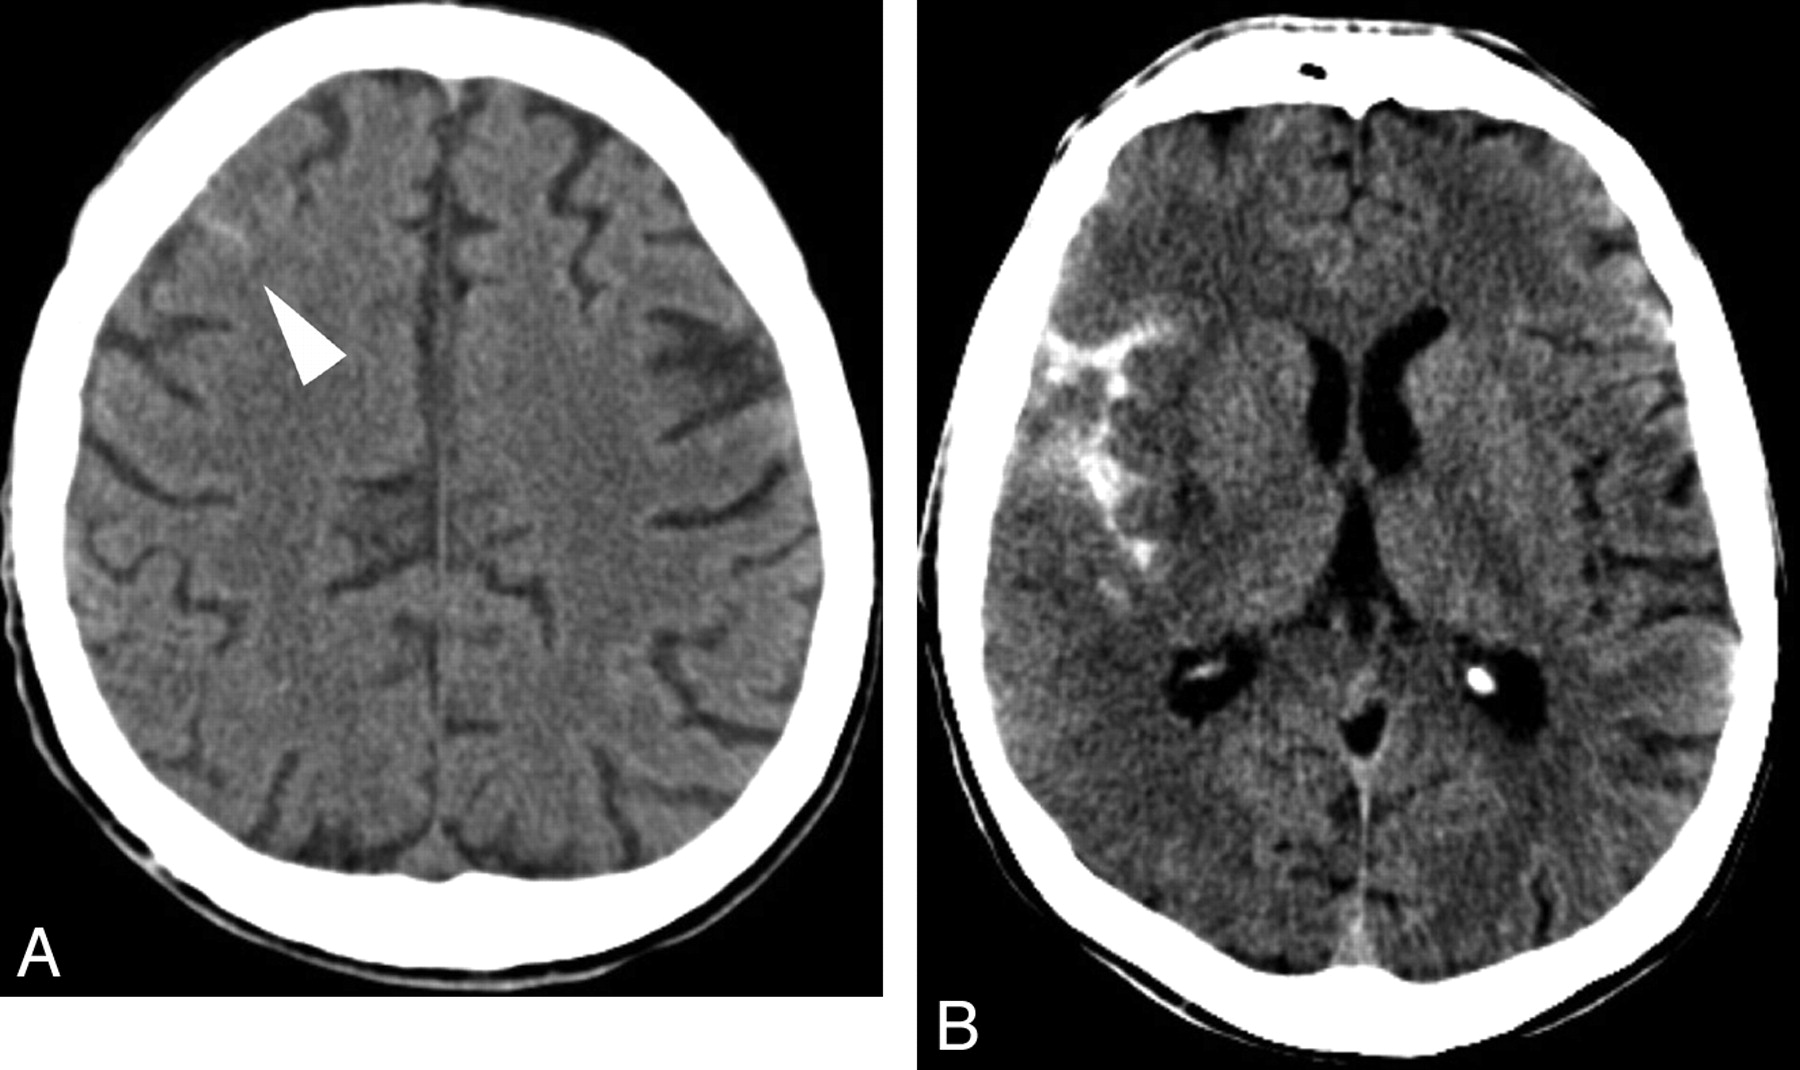

- Haemorrhage: Hyperdense areas. Classify as epidural, subdural, intraparenchymal, or subarachnoid based on location and shape.

| Subdural haemorrhage | Crescent-shaped hyperdensity along brain surface, crossing suture lines, may track over a large area. Often associated with mass effect and possible midline shift. |

| Epidural haemorrhage | Biconvex (lens-shaped) hyperdensity that typically does not cross suture lines. May cause mass effect and midline shift; commonly related to skull fracture. |

| Intracerebral / intraparenchymal haemorrhage | Hyperdense collection within brain parenchyma with variable mass effect. Appearance depends on location and size; may extend into ventricles. |

| Subarachnoid haemorrhage (SAH) | Hyperdensity in sulci, basal cisterns, or fissures. Diffuse SAH shows widespread cortical sulcal hyperdensity; localised SAH may be focal in a specific sulcus or cistern. |